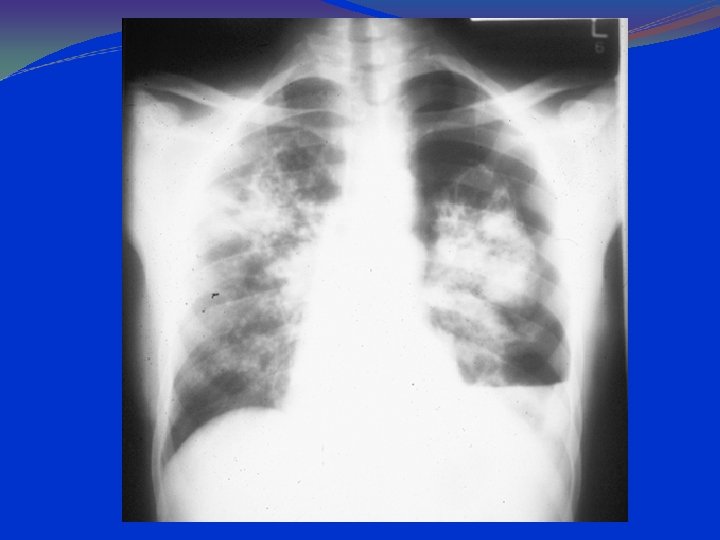

PCP: CXR Findings 90 -95% have pulmonary infiltrates. Combined interstitial & alveolar infiltrates. Predominantly at bases and centrally. Pneumothorax can be present. Lace like appearance.

PA Chest Radiograph Demonstrates bilateral, perihilar, R > L, ground glass opacities

PA Chest Radiograph Progressive disease showing extensive ground glass opacification with consolidation